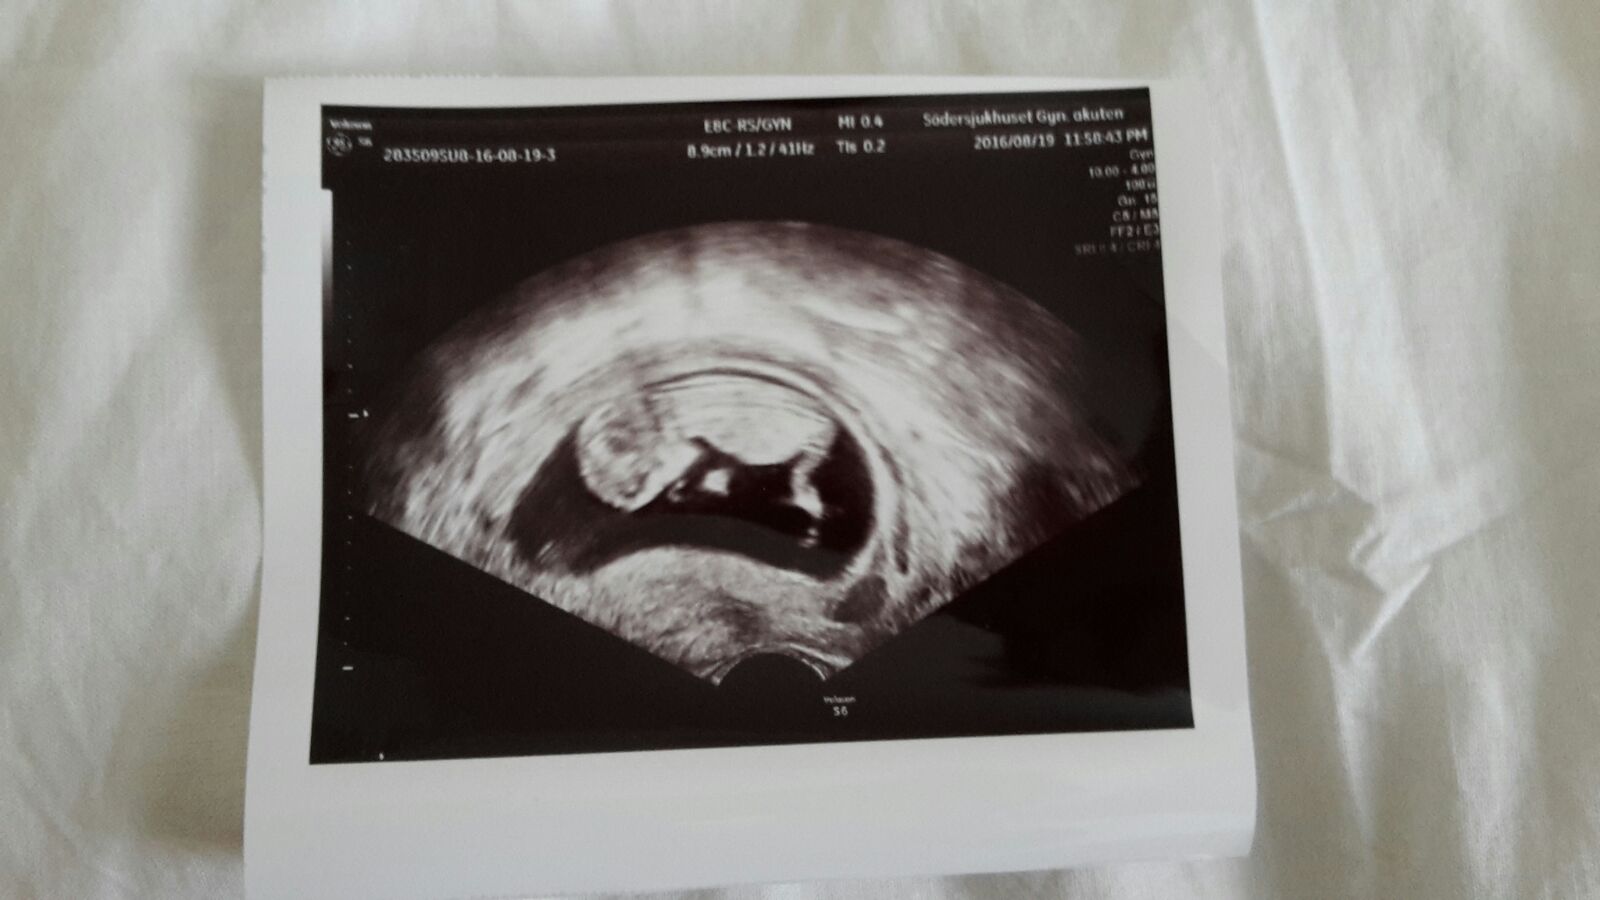

Here's your first picture baby love. Our tiny little baby.

We got worried when I had some bleeding so we had to check it out. In the middle of the night in Stockholm city where we were at the moment. 1 tiring hour waiting for our turn in the emergency room, then finally the doctor came and get us.

You just loose your breath when you hear all the things that can happen.. miscarriage... that would be the worst.. It's amazing how you can love something you haven't even meet.

Then we saw you.. so alive and kicking with your little legs and your heart beats so fast. There's no words to discribe the joy we felt. Only tears of happiness..

Love you baby love.. keep growing in mommy's belly. Can't wait to see you soon..